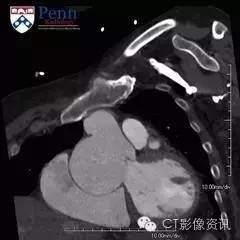

病史 53岁,男性,有心脏杂音及异常超声心动史。为了进一步评估遂转入CT室行CT血管造影。

冠脉CT图像如下

1.图中箭头所指的部位是?(单选)

3.异常的位置是在?(单选) 窦管交界处 右冠状动脉窦 左冠状动脉窦 无冠状动脉窦